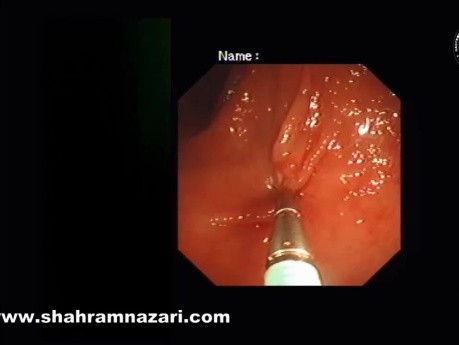

Myomectomie de Heller pour Spasme Oesophagien...

Le spasme œsophagien distal symptomatique (anciennement appelé spasme œsophagien diffus) fait partie d'un spectre de troubles moteurs caractérisés par des contractions non propulsives et des contractions...